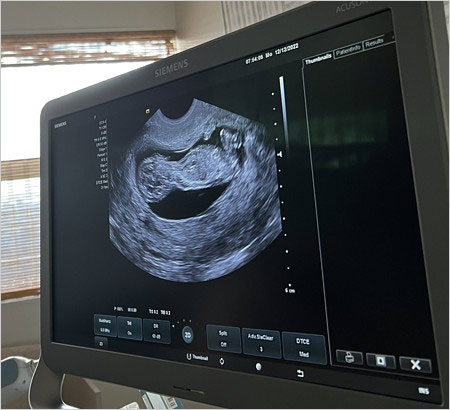

大坂なおみ選手はエコー写真も公開した上で、英語と日本語で第1子妊娠を発表しており、「ここ数年は色々な意味で極めて困難でもあり又楽しくもありました。」と書き出し、「将来に向けて沢山楽しみな事があります。それらの一つには自分の子供が私の試合を見て、『あれが私のママ』と誰かに言う事です(笑)2023年は私にとって色々勉強する年となります。来年明けから皆さんに会える事を期待してます、2024年の全豪には出場しますので。永遠に愛してます。」

と綴り、第1子妊娠と来年に復帰することを発表しています。

<↓の画像が、大坂なおみ選手が公開した赤ちゃんのエコー写真>